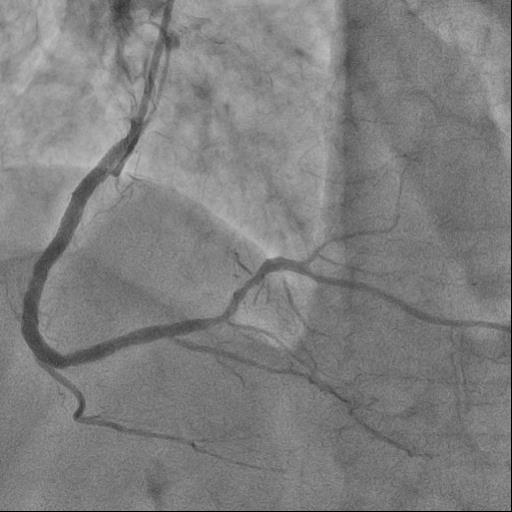

Angiography Right coronary artery dominance LEFT CORONARY ARTERY (LCA): trunk of the left coronary artery: uneven contours along the entire length. Left Anterior descending artery (LAD): uneven contours, stenosis in medial part by 80%. Circumflex artery (LCX): uneven contours along the entire length. RIGHT CORONARY ARTERY (RCA): uneven contours in the proximal segment, ¬³hronic total occlusion, the post-occlusionportion is fairly filled through intersystem collaterals.

The guide catheter was selectively placed at the RCA orifice, several attempts at antegrade recanalization were performed, after 10 minutes a decision was made to perform retrograde recanalization of the RCA, Sion Blue with the support of a Corsair 150cm microcatheter was successfully introduced through the septal branch into the middle segment of the RCA, escalation to Gaya 2 was performed and recanalization of the RCA was performed. Tip-In was performed in the antegrade guide catheter, the retrograde coronary guide was fixed with a balloon catheter. The retrograde microcatheter was advanced into the proximal segment, however, when performing Corsair, its defragmentation occurred, and the tip of the microcatheter itself was torn off. A decision was made to perform repeated recanalization of the RCA in a new lumen. Recanalization was successfully performed, then Tip-In was performed into the antegrade microcatheter and its successful passage beyond the occluded area. Balloon angioplasty and stenting of the RCA under OCT control with vFR.